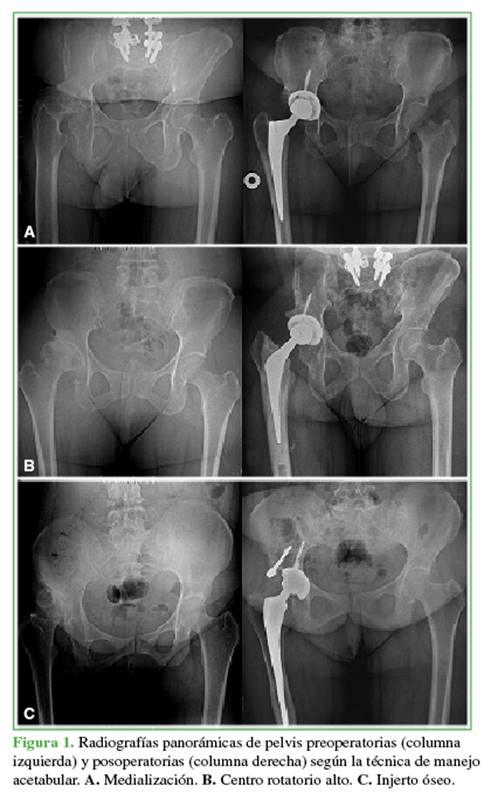

En cuanto al manejo acetabular quirúrgico utilizado, se realizó medialización en el 58% (29 casos), un centro de rotación alto en el 38% (18 casos) y un injerto óseo en el 8% (3 casos) (Figura 1). La muestra fue dividida en dos grupos: ≤46 años (grupo 1) y >46 años (grupo 2) (Tabla).